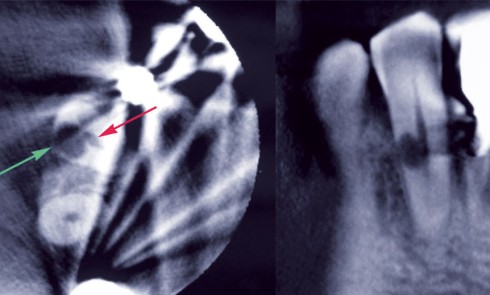

Si en 1900, la pratique de la radiologie au cabinet dentaire était déjà possible, elle n’était ni généralisée, ni réglementée....